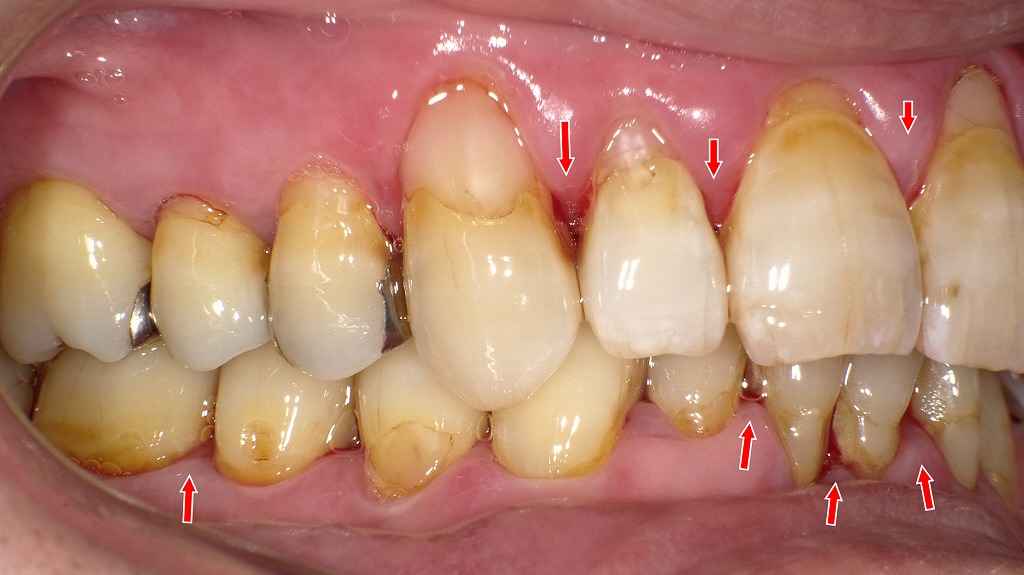

また治癒力が下がるため、炎症が長引きやすく、歯周病が進行しやすくなります。② 右側写真:縁下歯石と歯肉の炎症反応の増大

歯の根元にプラークと縁下歯石が多く付着し、歯肉が赤く腫脹。

糖尿病により炎症反応が増幅し、出血しやすい歯肉の典型例です。右側の画像では、以下の所見が明確です。

- 歯肉が丸く腫れ、縁下歯石による歯肉縁の赤みと出血

- 歯の根元に付着したプラーク・バイオフィルム

- 歯肉の引き締まりが弱く、糖尿病特有の浮腫状の歯肉がみられる

縁下歯石は歯周病を加速させるため、糖尿病患者では特に**早期のスケーリング・ルートプレーニング(SRP)**が重要です。

③ 左側写真:広範囲にわたる歯周炎の兆候

広範囲に歯肉の腫れと発赤があり、歯間部には隠れた出血点が多数。

血糖コントロール不良が歯周病の進行を加速させています。左側の画像でも、

- 歯頰側の歯肉がぷっくりと腫れている

- 歯間の歯肉が赤く、**隠れた出血ポイント(BOP)**が多数

- 歯の根元の茶色い付着物はプラーク~縁下歯石の混合

糖尿病による血流障害や免疫力低下により、炎症がさらに助長されている所見として典型的です。